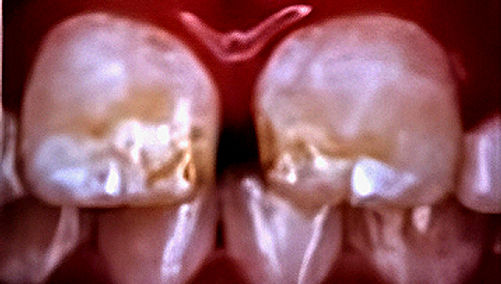

Fluorosis gigi adalah kelainan yang termasuk hipoplasia email, yakni gangguan pada pembentukan lapisan email gigi. Kondisi ini menyebabkan perubahan bentuk dan warna gigi, yang bisa tampak sebagai bercak buram hingga kecokelatan. Fluorosis terjadi akibat asupan fluoride yang berlebihan, baik secara sistemik maupun lokal, selama masa pembentukan gigi, terutama pada anak-anak di bawah usia 8 tahun. Pada kasus ringan, muncul bintik putih; namun pada kasus berat, email gigi bisa menjadi kasar atau berlubang kecil.

- Sedang (TFI 4–6): bercak putih lebih luas, mulai muncul warna cokelat,

- Berat (TFI 7–9): warna berubah drastis, permukaan email kasar, dan dapat berlubang.